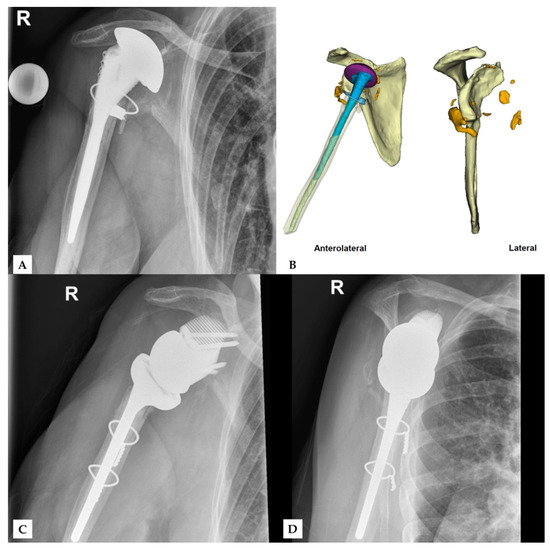

Figure 1, Figure 2 and Figure 3 show an example procedure on a case with severe bone loss due to glenoid loosening after primary anatomical TSA. Septic loosening must be excluded using a two-time procedure with sonication and tissue sampling. Radiographs in the anteroposterior and axial directions and an additional CT scan are necessary before surgery. The CT scan must be performed according to the manufacturer’s specifications to assess the bone stock and plan an adequate prosthesis. The original glenoid is reconstructed using statistical shape modelling, and an appropriate centre of rotation is proposed [8]. The position of the screws is proposed depending on the best direction and maximum possible length of the intraosseous screw length according to bone stock and quality.

Figure 1. One case of revision reverse total shoulder arthroplasty severely damaged glenoid in the setting of implant loosening after anatomical TSA. Preoperative X-rays were performed in the (A) anteroposterior and (B) axial directions. (C) The surgical procedure consisted of two-time revision with explantation of the anatomical prosthesis and exclusion of infection via sonication and tissue samples. (D) Surgery using a custom-made glenoid component was performed after confirmation of aseptic loosening.